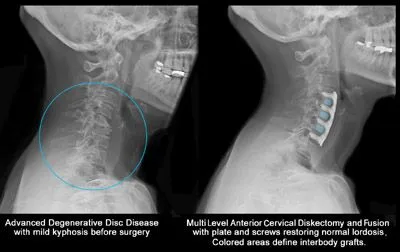

The X-ray below shows degenerated discs on the leftbefore surgery. On the right is an X-ray of the discs after traditional spinal fusion surgery.